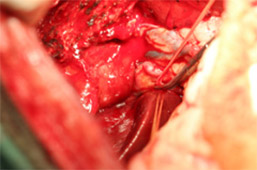

治療:飼い主様の希望により、肝臓腫瘍摘出手術と胆嚢切除手術行いました。肝臓腫瘍摘出は特に血管系の処理が重要で基本的な結紮技術はもちろん、超音波乳化吸引装置や血管シーリング装置などを駆使し血管を一つずつ処理して行きます。

肝臓腫瘍と胆嚢を摘出した写真です。肝臓腫瘍摘出には超音波乳化吸引装置を使用し、かなり安全に手術が可能でした。

胆嚢内にはゼリー状の内容物が詰まっていました。手術後は2日後から食欲も改善し、状態も改善しました。病理検査で肝細胞癌との診断でしたが、手術で切除しきれているとのことで、今後は無治療で経過観察中です。